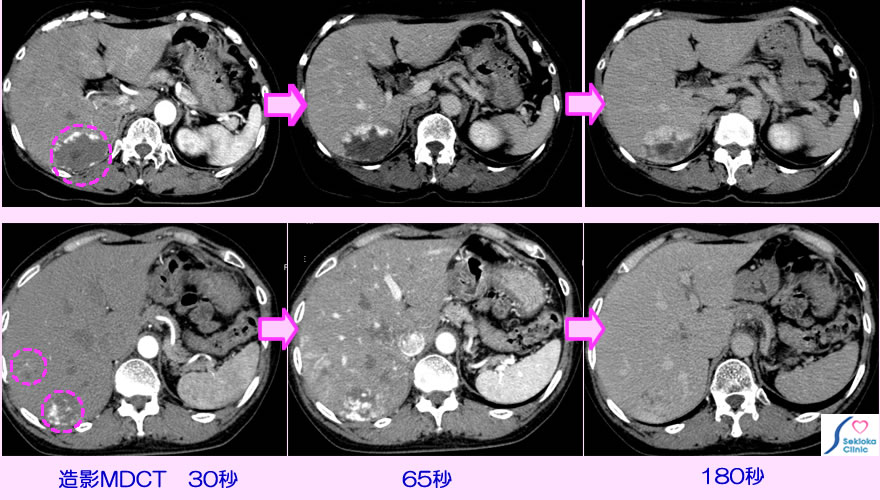

肝血管腫 CT画像

腹部エコー検査で偶然見つかる。超音波エコーはある程度特徴的で推測できるが鑑別のため造影CT検査を行う。造影剤注入後の腫瘍部の染まり方の変化の特徴から他の腫瘍と鑑別する。

2例の造影CTの時間的変化を示します。